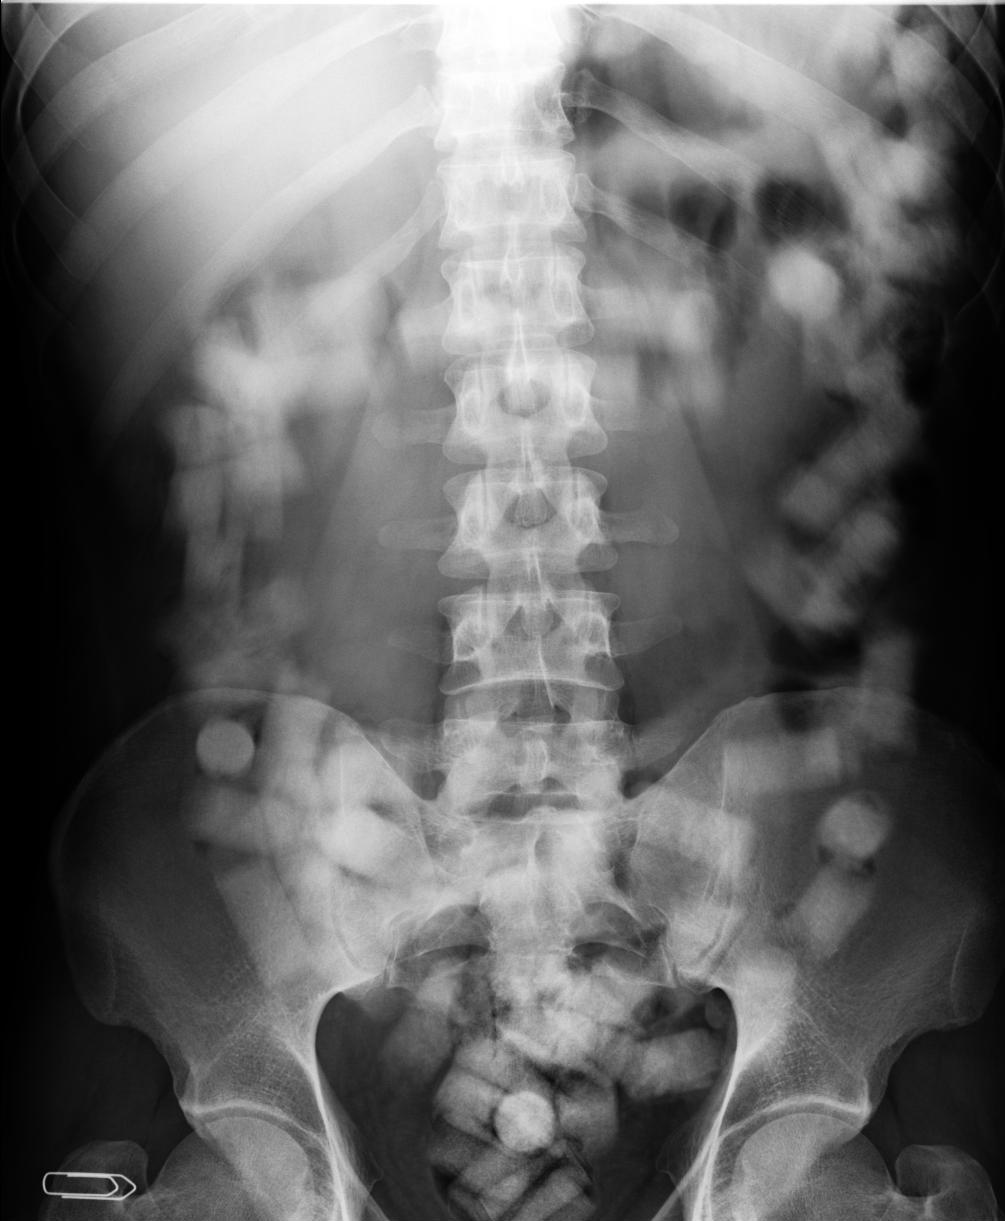

A Polícia Federal de Foz do Iguaçu, no oeste do estado, prendeu um paraguaio que havia ingerido 70 cápsulas de cocaína para levá-las até a Espanha, no último domingo (30). O paraguaio, de 35 anos, foi acusado de cometer tráfico internacional de drogas.

O paraguaio foi preso em flagrante e levado para o Hospital Municipal de Foz do Iguaçu, onde receberá medicação para expelir as cápsulas.